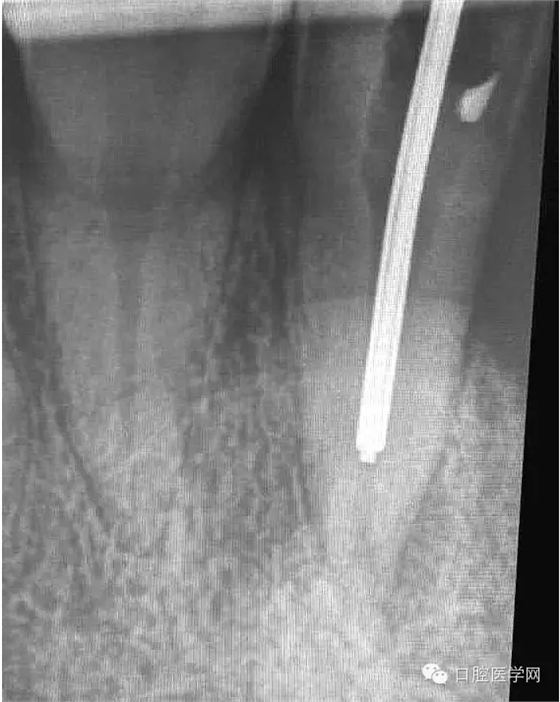

1.先根測(cè)根長,再用機(jī)擴(kuò)對(duì)根管進(jìn)行預(yù)備;

4.準(zhǔn)備放置橡皮障(由于拍片是較遠(yuǎn),所以,橡皮章暫時(shí)取下),去除暫封材料。在顯微鏡放大視野中,蔣調(diào)拌好MTA輸送至根尖部。